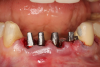

On the day of surgery, the plan was to extract teeth Nos. 21, 23, 24, 25, and 26, place 3.0 x 13-mm implants in the anterior region due to limited spacing, and place a 4.1 x 10-mm implant in the No. 21 extraction site. Before the extractions were performed, the No. 23 pontic was sectioned from the existing 2-unit cantilevered bridge utilizing ceramic and metal high speed rotary cutting burs ZR 6881 and H34L (Komet-USA), respectively. After removal of the pontic and extractions, the surgical guide was verified to be seating positively (Figure 36 through Figure 38). Surgical guide protocol was followed, and all implants were successfully placed and torqued to a value of greater than 35 Ncm (Figure 39 and Figure 40). All implants were placed without flapping, with the exception of No. 23. The flap was elevated to reposition lingual keratinized tissue facially for enhanced esthetic tissue profile. The implants were then prepared with a high-speed carbide bur (Komet-USA) with copious amounts of water (Figure 41 and Figure 42). The one-piece 3.0-mm diameter implant served the needs of the patient's spacing requirements. Inter-occlusal space requirements and path of draw were verified. The PMMA provisionals were air abraded and relined with crown-and-bridge material (Figure 43 through Figure 45).

Fig 41. Abutment preparation.

Figure 41

Fig 42. Occlusal view of prepared implants.

Figure 42